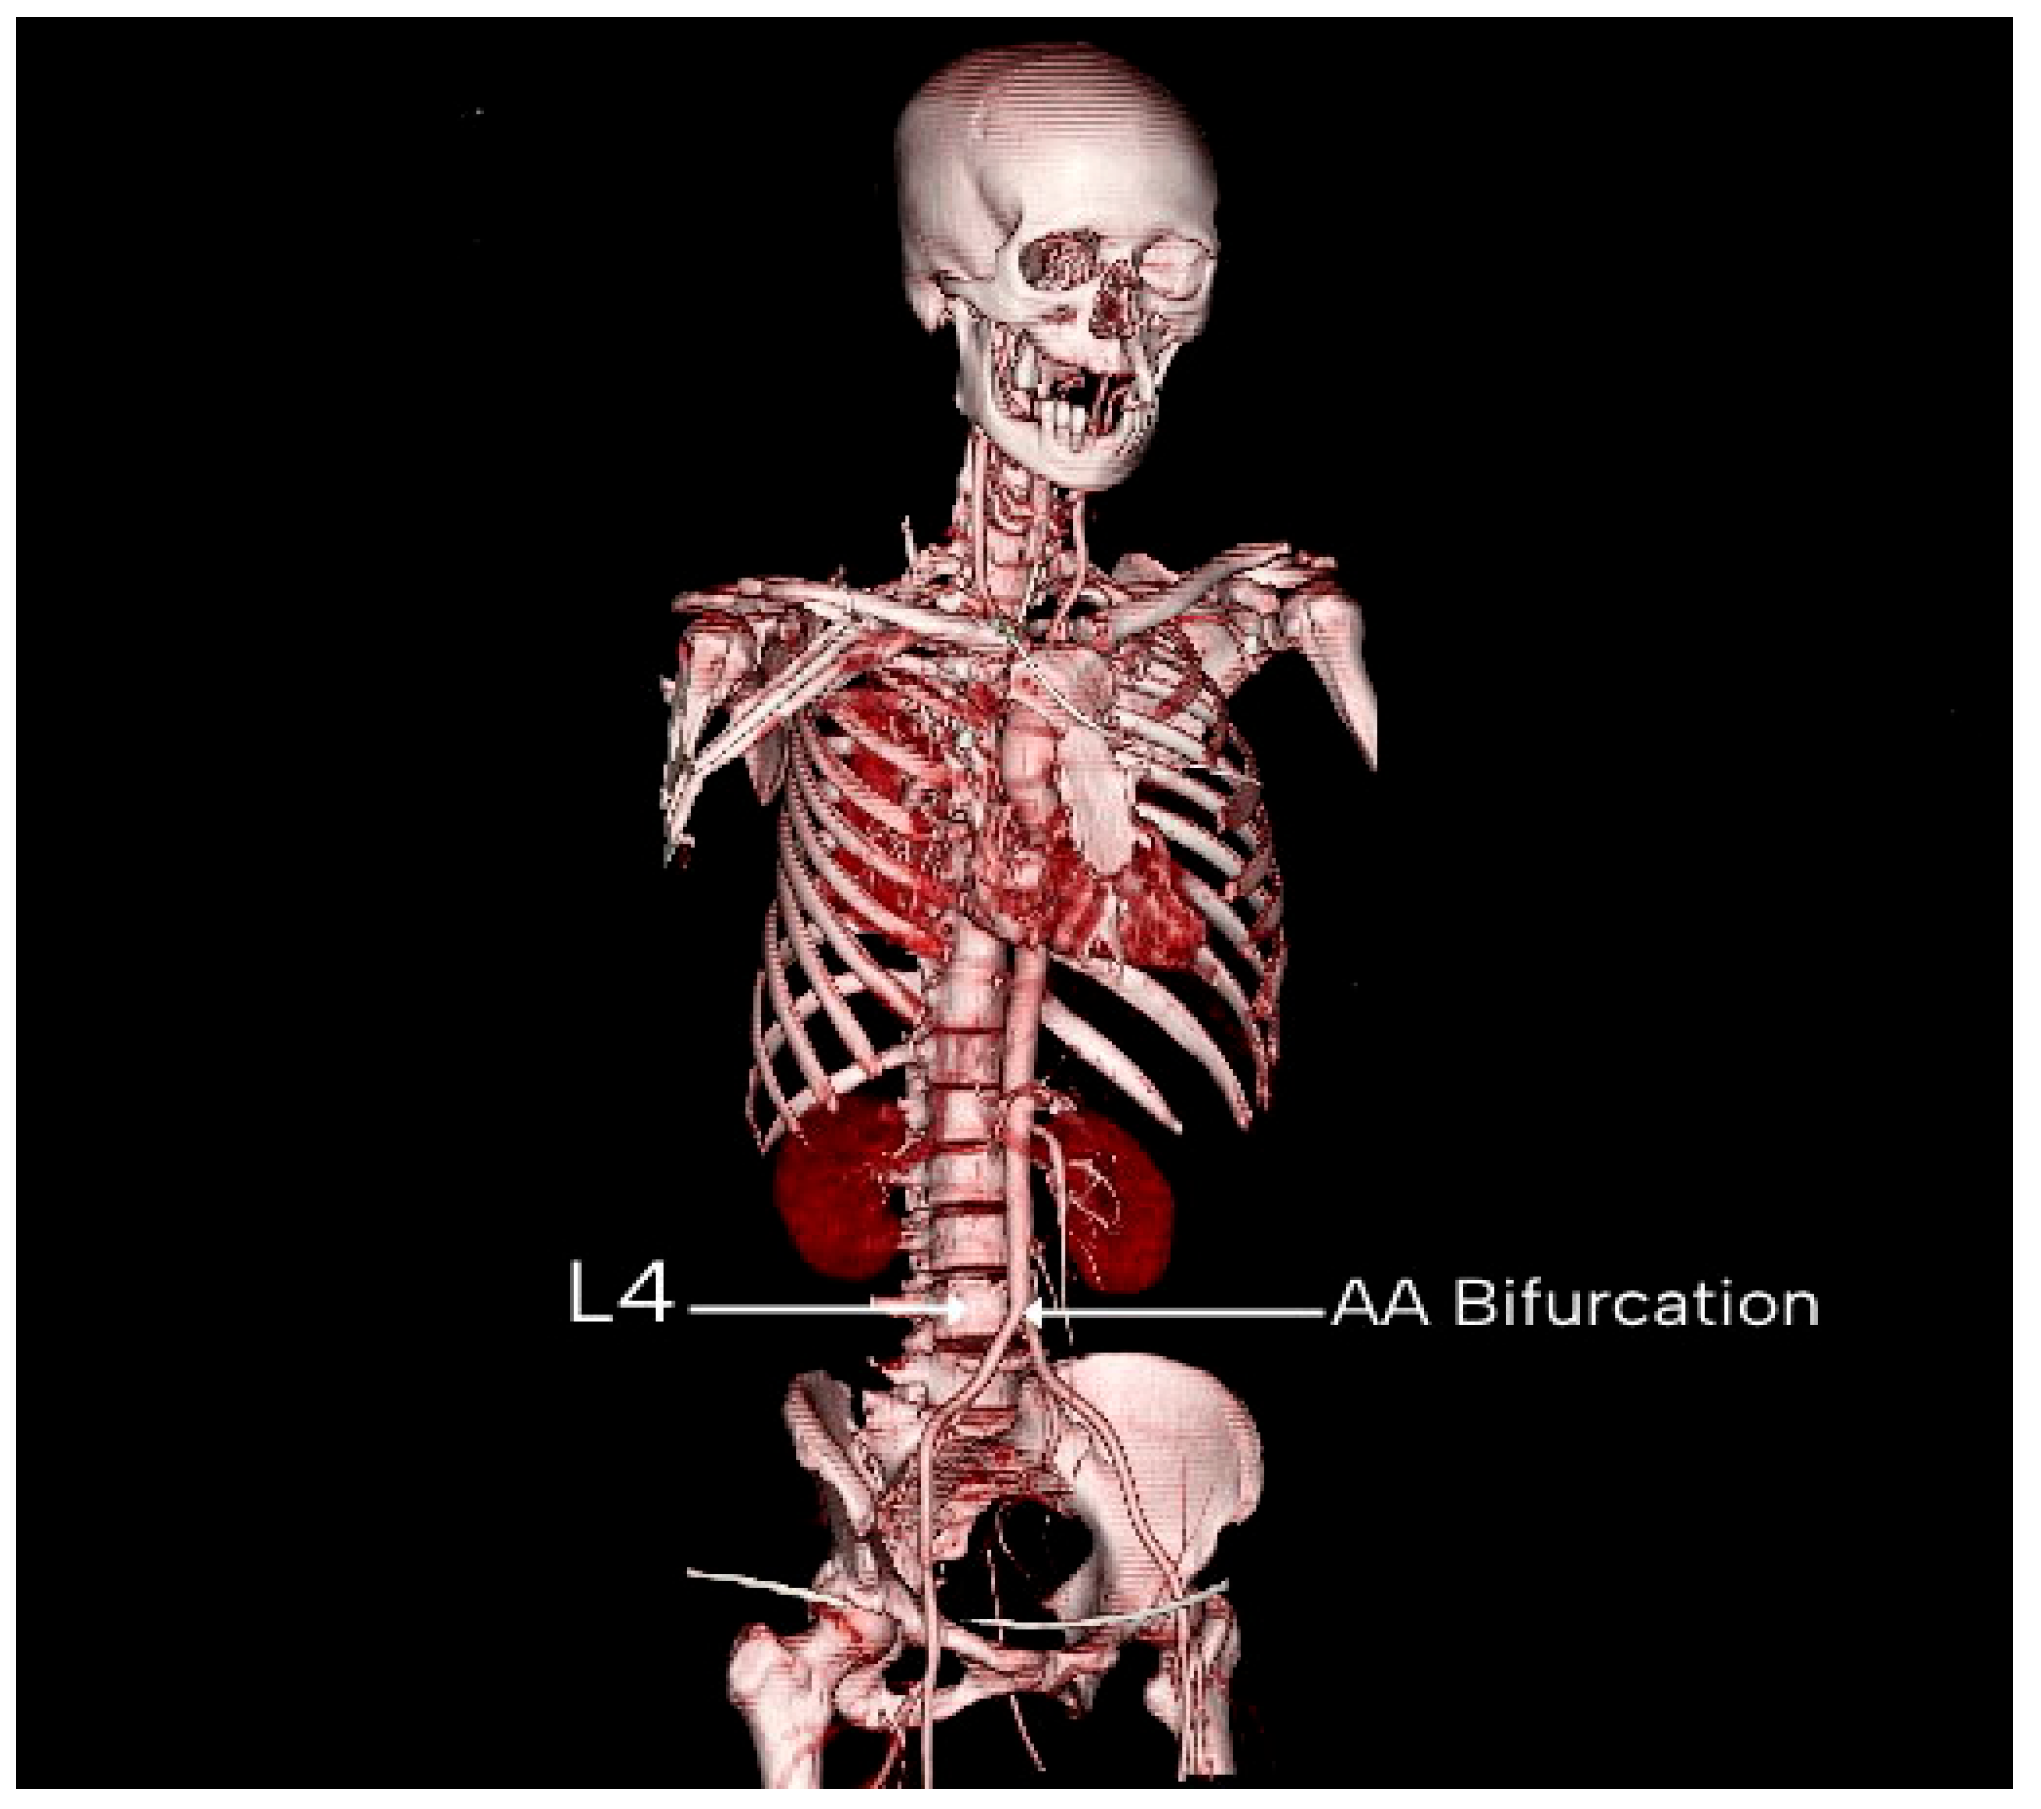

| Vertebral Level | Males | Females |

|---|---|---|

| L3 | 34 (23.61%) | 18 (32.14%) |

| L4 | 102 (70.83%) | 35 (62.50%) |

| L5 | 8 (5.56%) | 3 (5.36%) |

| Total | 144 (100%) | 56 (100%) |